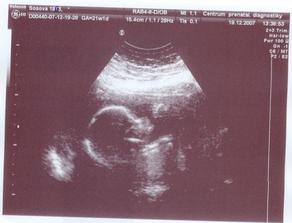

19. prosince nám na ultrazvuku řekli "no je tam pindík " - a tak budemem mít pindíka Danečka /